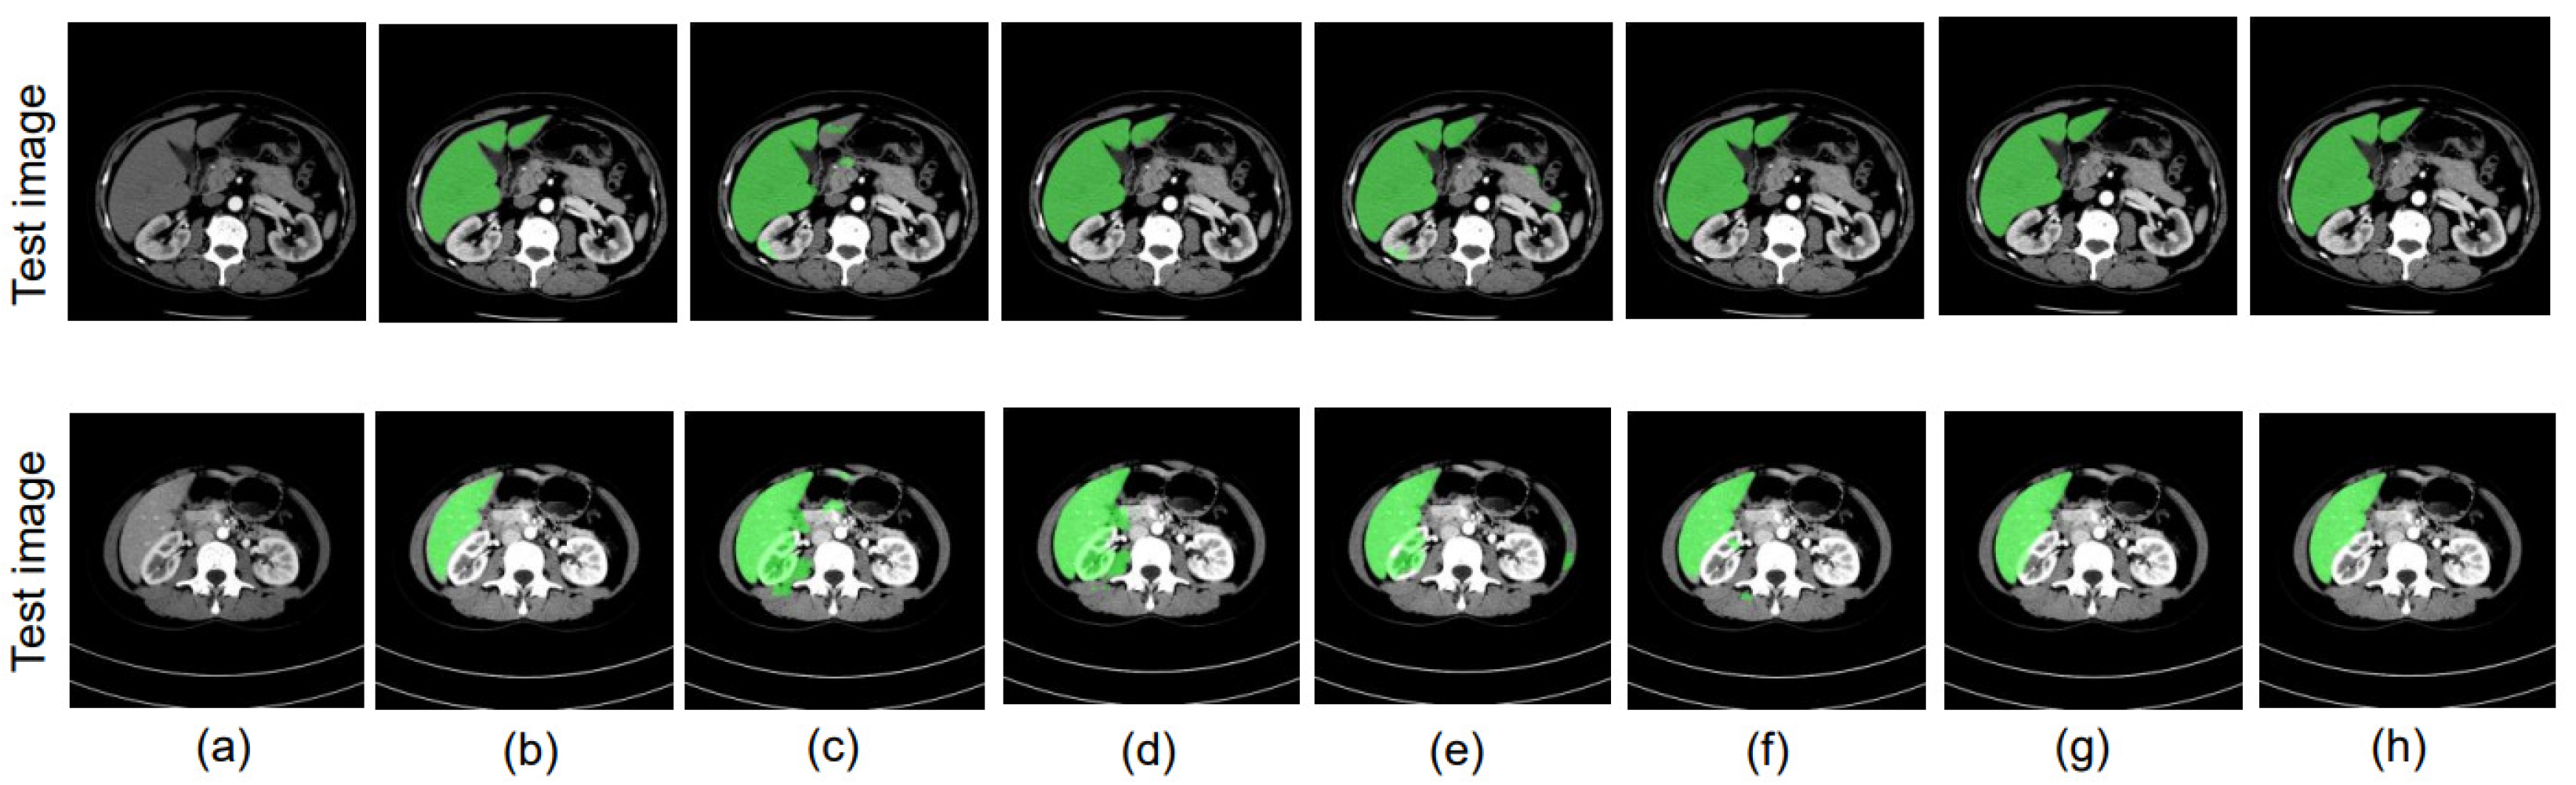

4.8. Ablation Study

4.8.1. Different Datacenter and Same Phase

4.8.2. Same Datacenter and Different Phase

4.8.3. Different Datacenter and Different Phase